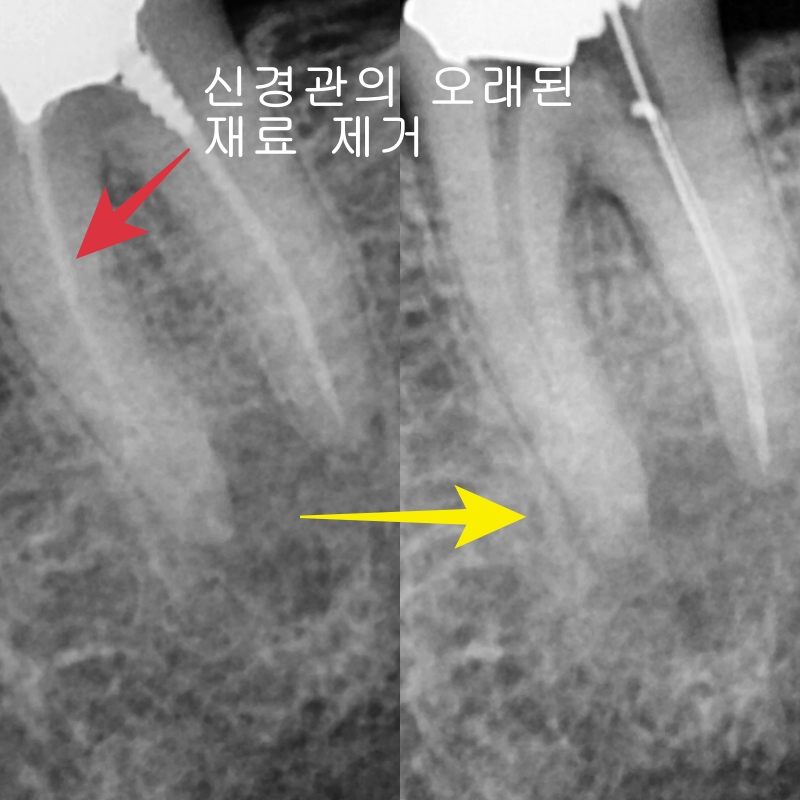

오래된 근관치료된 치아의 뿌리 쪽의 오래된 수복 재료는 완벽히 제거하기가 상당히 어렵습니다.

중간중간 사진을 찍어서 확인해가며 제거했고

운이 좋게도 기둥과 뿌리 안의 수복물을 제거할 수 있었습니다.

신경치료가 마무리된 후 엑스레이 사진입니다.

첫 번째 케이스와 마찬가지로 의도하지는 않았지만

뿌리 쪽으로 충전재가 뿌리를 감사고 있는 모습을 보이고 있습니다.